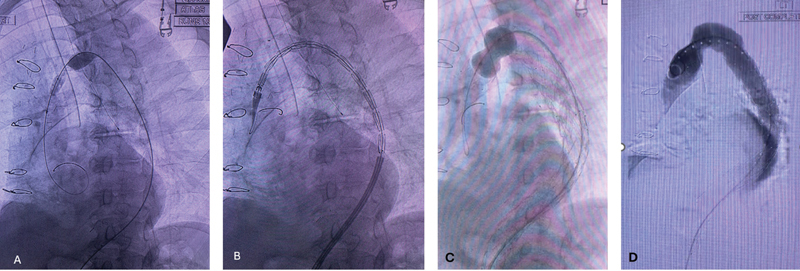

众所周知,脊髓缺血(SCI)是胸腹主动脉开放性和血管内修复术的并发症之一。围手术期增加脊髓灌注的措施,包括允许性高血压和放置腰椎引流管以控制脊髓压力,通常用于降低脊髓缺血的风险。围术期减少脊髓易受缺血性损伤的其他措施包括低体温、类固醇和输注纳洛酮。大多数病例会在手术后立即或数天内显现,并在采取上述措施后得到改善。我们描述了胸腔内血管主动脉瘤修复术后 20 个月出现延迟性 SCI 的罕见病例。

Spinal cord ischemia (SCI) is a well-known complication of both open and endovascular repair of the thoracoabdominal aorta. Perioperative maneuvers to increase spinal cord perfusion, including permissive hypertension and lumbar drain placement to control spinal pressure, are commonly used to reduce the risk of SCI. Additional perioperative measures to reduce the susceptibility of the spinal cord to ischemic insult include hypothermia, steroids, and naloxone infusion. Most cases manifest immediately or within days of surgery and improve with the aforementioned maneuvers. We describe a rare occurrence of delayed SCI 20 months after thoracic endovascular aortic aneurysm repair.